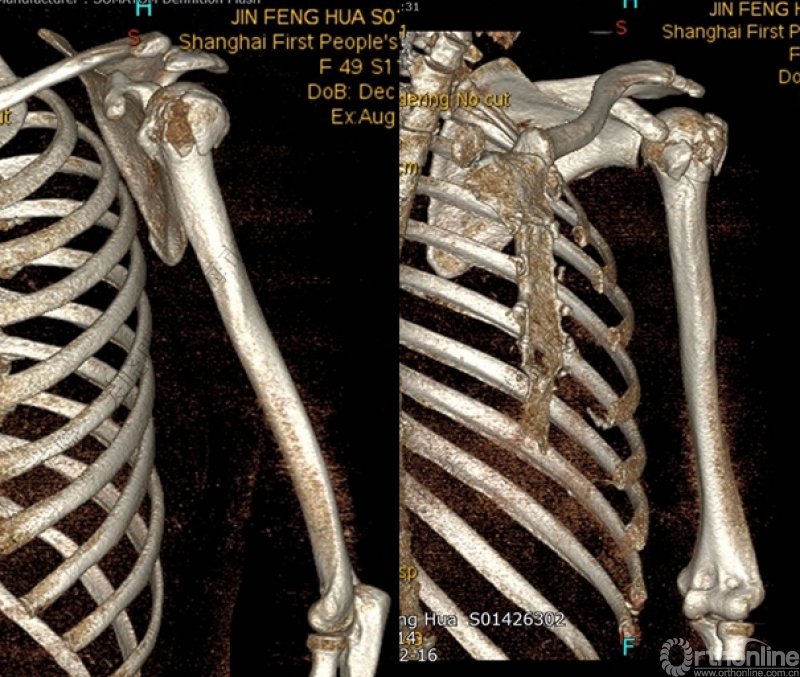

警惕孤立性向下移位的大结节骨折

外翻压缩型肱骨近端骨折

钢板固定

X线是孤立性向下移位的大结节,一定要小心,多伴有肱骨外科颈骨折